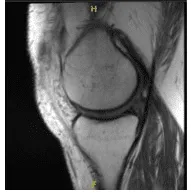

MRI was presented and shown An MRI was provided, which revealed a mild sprain of the medial collateral ligament but no tears. A 0.5 cm para meniscal cyst is linked with a longitudinal vertical tear affecting the outer third of the body and the posterior horn medial meniscus. There was mild fraying of the free border of the lateral meniscus. There was a tiny joint effusion and a lymph node in the popliteal fossae with an unknown etiology.

MRI presented to post operative visit, no visibility of the cyst